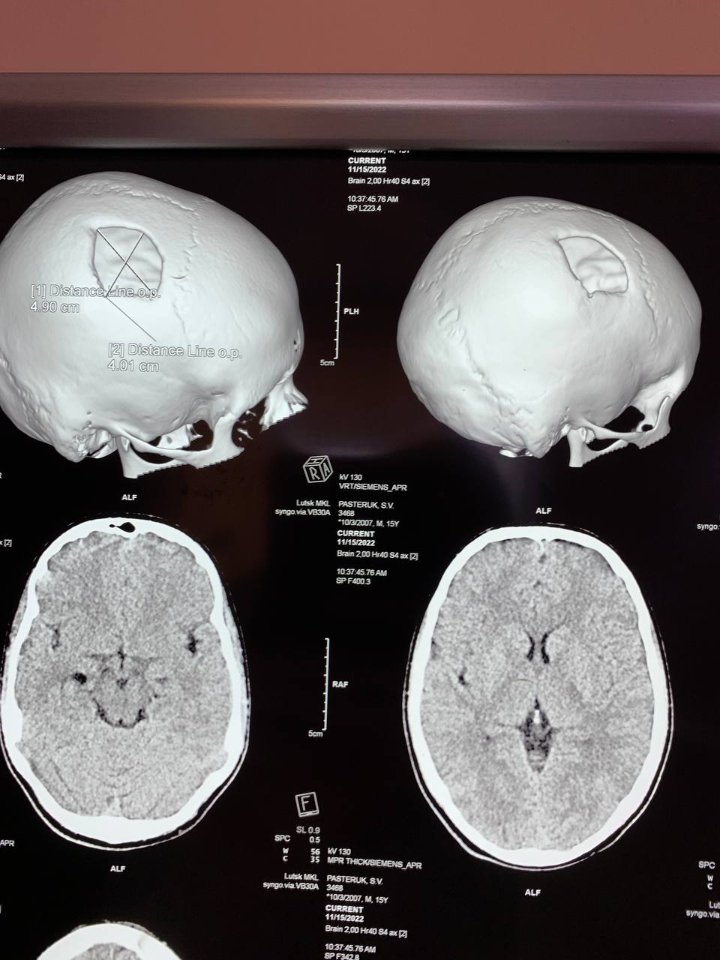

Рівненські лікарі встановили в череп 15-річному волинянину титанову пластину

Лікарі Рівненської обласної дитячої лікарні зробили складну операцію для 15-річного хлопця з Волинської області.

Волинянин дев'ять місяців тому отримав складну черепно-мозкову травму і рівненські медики виконали йому краніопластику, - повідомляють на сайті установи.

Пошкоджену частину черепної коробки закрили спеціальною титановою пластиною, яка повторює кісткові структури черепа, захищає мозок від ушкоджень.

Оперативне втручання провели: лікар-нейрохірург дитячий Сергій Романчук та лікар-хірург дитячий Ігор Сегін.

Операція пройшла успішно, хлопець на третю добу був виписаний додому.